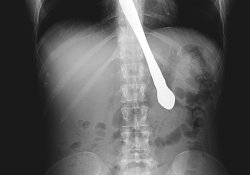

30-летняя жительница американского города Атланта на продолжении многих лет страдала булимией. Наконец, обращение к врачу принесло успех. Но во время демонстрации результата сестре, бывшая больная не смогла сдержать смех – и поплатилась за это.